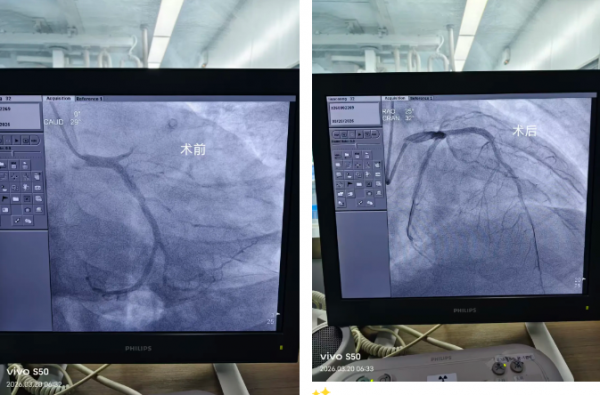

我院在院前接诊阶段便已启动急诊绿色通道,依托胸痛中心快速响应机制,待患者生命体征稍稳后,各相关科室高效联动,无缝衔接急诊抢救室与导管室,快速护送患者接受急诊血管介入治疗。内五科团队精准研判、娴熟操作,迅速开通堵塞血管、恢复心肌供血,牢牢把握救治关键时机。

经过急诊科、内五科、导管室等多科室规范高效的协同处置,患者生命体征趋于平稳,现已安全转入重症医学科进一步监护治疗。